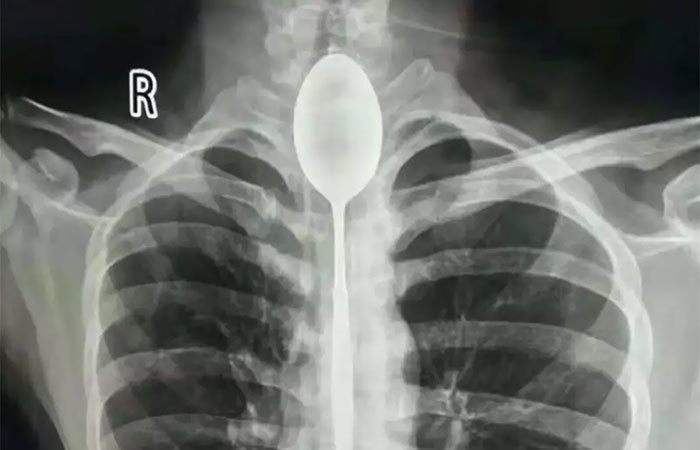

Подборка рентгеновских снимков, которые наглядно показывают, что от нас скрывает природа

Самые занимательные рентгеновские снимки, показывающие, что скрыто от глаз человека

Сегодня открытие немца используют во многих сферах жизни, начиная с медицины и заканчивая таможней. Собрали для вас самые занимательные рентгеновские снимки, показывающие, что скрыто от глаз человека.